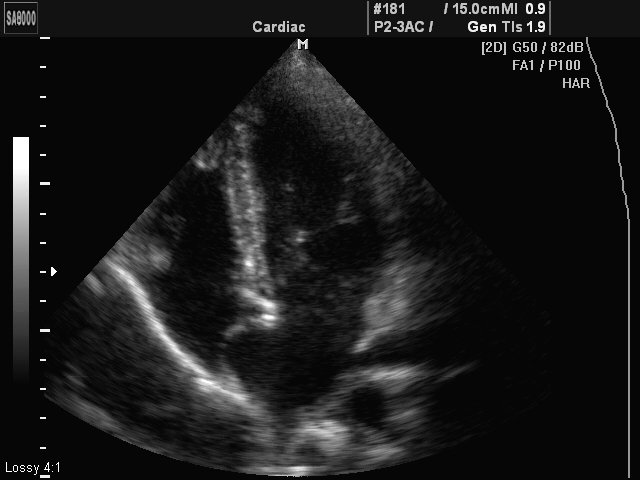

Aneurismus interatrium septum, B-mode (echogramm №429)

[RU] Ultrasound image №429: Heart (aneurismus interatrium septum, R-type) in B-mode.

Echogramm was received by ultrasound scanner SonoAce-8000 (out of production).